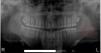

Case report17-Year-old patient (T.P.V.) with melanoderma was referred by his orthodontist for extraction of teeth 38 and 48 and a possible supernumerary tooth present in the left posterior mandibular region. Panoramic radiograph showed the presence of a well delimited, hyperdense, rounded structure near the mandibular angle, with approximately 10mm in diameter, overlapping the bone structures and the mandibular canal (Fig. 1). During the anamnesis, the patient reported no discomfort, pain or swelling. On clinical intraoral examination, no abnormality was observed. Milking maneuver was performed in the parotid gland and the salivary flow was found to be normal and with no pus. However, on the extraoral examination, during palpation of lymph nodes and bidigital palpation of the cheek, it was observed the presence of a rounded, firm, mobile nodule, under the skin at the lateral region of the mandible angle on the left side (Fig. 2). For a better assessment of the location and diagnostic hypothesis, it was performed a computerized tomography, which revealed the extra-osseous location of the lesion in the soft tissues laterally to the left mandibular angle (Fig. 3). The diagnostic hypotheses for such an alteration were sialolith and changed lymph node. During surgical planning, excisional biopsy was chosen, under local anesthesia, in an outpatient setting. The patient underwent extra-oral infiltrative anesthesia and it was performed a linear incision in skin, followed by divulsion of the flap by planes with Metzenbaum scissors (Fig. 4). Incision on the tissue which covered the nodule allowed the removal of the round solid body with 10mm in diameter (Fig. 5). The wound was sutured with Nylon (5-0) and the specimen was sent for histopathological examination. During the clinical follow-up, the patient recovered without any complications. After routine histology, the department of pathological anatomy of the subject Oral Pathology (Federal University of Alfenas/ Unifal-MG) reported that the microscopic sections revealed that the fragment consisted of concentric laminations with slight differences in color, separated by reversal lines; peripherally it was observed fibrous connective tissue that was dense, slightly cellularized and vascularized. The diagnosis was sialolith. After 30 months no recurrence of the lesion was observed, as shown in the panoramic radiograph (Fig. 6).

After reviewing the CT images, it was possible to determine the precise location of the sialolith, which was located in the soft tissue, near the angle of the jaw on the left side, superficially to the masseter muscle and below the parotid duct. Thus, the surgical procedure can be planned and carried out without major complications for the patient. In addition, histopathological diagnosis allowed to conclude that the foreign body was a sialolith located in the parenchyma of the parotid gland in its superficial surface, characterizing an atypical location of salivary calculus since the ductal location is the most common one. Therefore, this case report adds information to the small number of described cases of sialoliths developed in the parotid gland, especially in its glandular portion, emphasizing that despite the majority of salivary calculi present very peculiar characteristics, some may have an atypical location and be radiographically confused with other structures, such as intraosseous pathologies or retained tooth. The authors also emphasize the importance of computerized tomography imaging for the resolution of this case, which is considered the best method for locating mineralized structures of difficult diagnosis and/or delimitation.